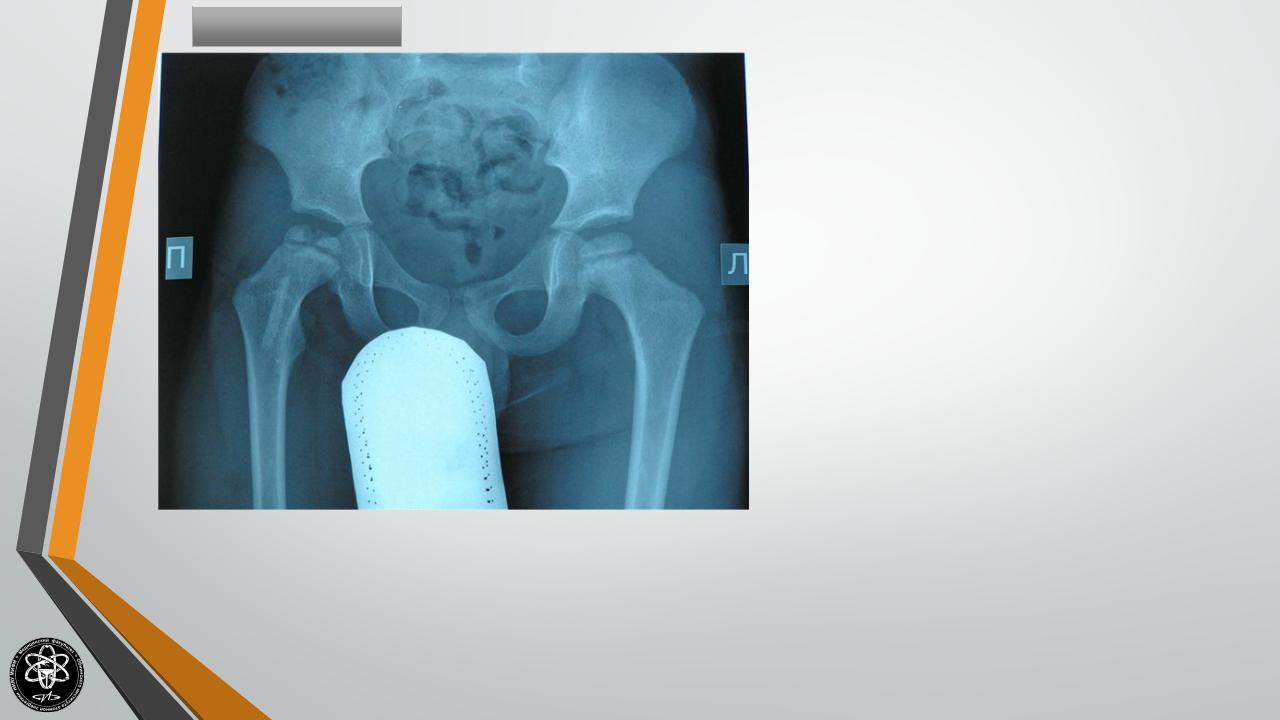

Болезнь Пертеса

Полное название – болезнь Легга-Кальве- Пертеса.

Поражает головку тазобедренной кости. Чаще развивается у мальчиков в возрасте 4-9 лет. Возникновению остеохондропатии может предшествовать (не обязательно) травма области тазобедренного сустава.

Болезнь начинается с легкой хромоты, к которой позже присоединяются боли в области повреждения, нередко отдающие в область коленного сустава. Постепенно симптомы остеохондропатии усиливаются, движения в суставе становятся ограниченными. При осмотре выявляется нерезко выраженная атрофия мышц бедра и голени, ограничение внутренней ротации и отведения бедра. Возможна болезненность при нагрузке на большой вертел. Нередко определяется укорочение пораженной конечности на 1-2 см, обусловленное подвывихом бедра кверху.

Остеохондропатия длится 4-4,5 года и завершается восстановлением структуры головки бедра. Без лечения головка приобретает грибовидную форму. Поскольку форма головки не соответствует форме вертлужной впадины, со временем развивается деформирующий артроз.

Для того, чтобы обеспечить восстановление формы головки, необходимо полностью разгрузить пораженный сустав. Лечение остеохондропатии проводится в стационаре с соблюдением постельного режима в течение 2-3 лет. Возможно наложение скелетного вытяжения. Пациенту назначают физиовитамино- и климатолечение.

При нарушении формы головки бедра выполняются костно-пластические операции.